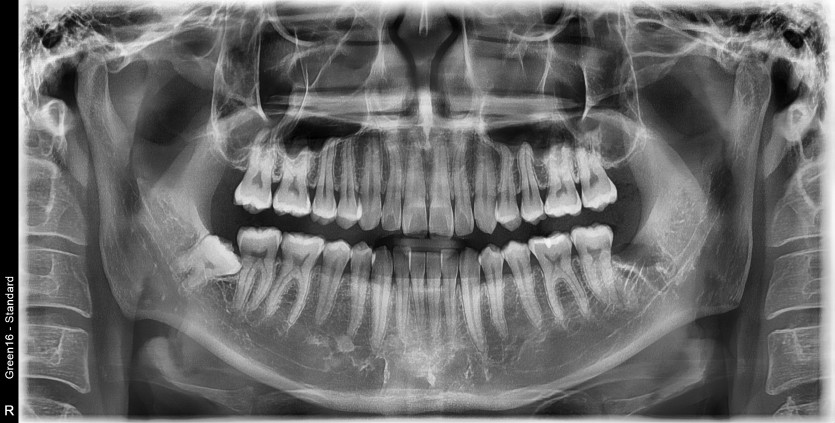

#38 사랑니 발치

구강 외과 전문의가 당일 발치했습니다.